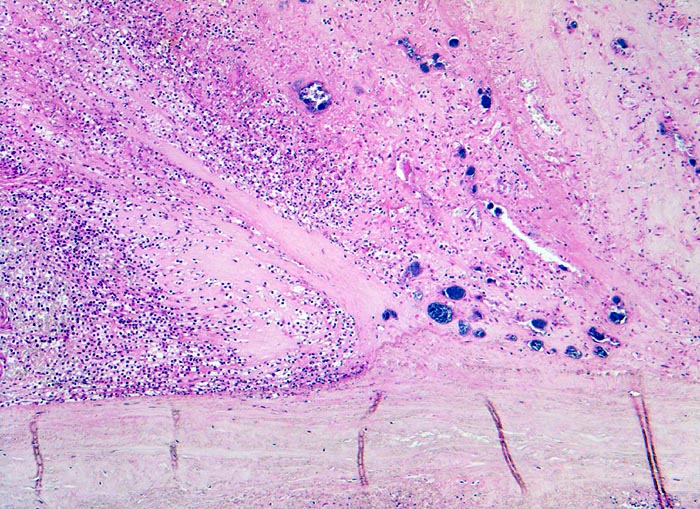

Morphologische Merkmale:

• Ulzerierte Aortenklappe(ulcerosa).

• Dem ulzerierten Klappengerüst aufgelagerte polypöse Vegetation aus Fibrin und Granulozyten durchsetzt von blauen Kokkenbakterienkolonien (polyposa).

• Ausgedehnte frische Koagulationsnekrose (unsichtbare Zellkerne, Infiltrate neutrophiler Granulozyten) des linken Ventrikelmyokards unterhalb der Klappe.

• Mehrere septikopyämische Streuherde (blaue Bakterienhaufen in intramyokardialen Blutgefässen umgeben von Mikroabszessen).

Histologisch findet sich bei ulzeropolypöser Endokarditis ein Fibrin-Thrombozytenthrombus, welcher von Bakterien durchsetzt ist (=Vegetation). Die Vegetation sitzt auf einem Klappendefekt an dessen Basis Granulationsgewebe einzusprossen beginnt, welches den Thrombus organisiert. Klappendefekte, Gefässeinsprossungen, verdickte Sehnenfäden (> 2848) oder Kommissurenverwachsungen (> 8389) der Taschenklappen weisen morphologisch auf eine abgeheilte Endokarditis hin.